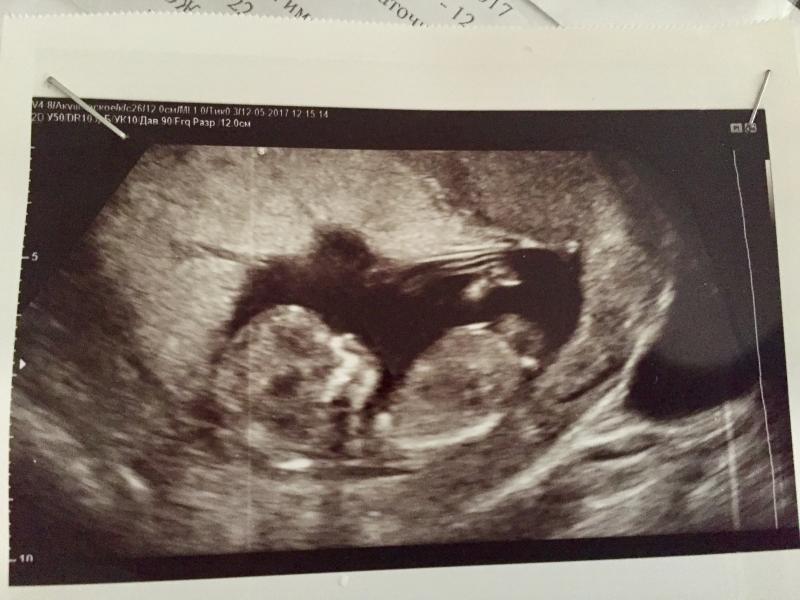

❗️В продолжении вчерашнего кошмира❗️Сегодня была у генетика в РКБ, послала на полный скрининг 1 триместра: повторно УЗИ + кровь. Сделала там же сразу в РКБ. Кровь будет готова в понедельник. По УЗИ показатели следующие (делала Токтарова по животу): ТВП 2,7 , длинна носовой кости 2,3 т.е. Почти норма. Вчера делала УЗИ у Юсупова трансвагинально:ТВП 3,8, нос 1,8. Риск хромосомных аномалий!!! Вот кому верить - непонятно. Жду понедельника.

@aigulka1991, Токтарова говорит, что не видит ничего плохого. Даже сердцебиение сказала 155, а не 147 как вчера. Генетик горит рано радоваться, надо кровь смотреть

Тут лучше кровь смотреть,а не узи.Узи имеет хорошие погрешности.Тем более вариант проведения узи разный.И ребенок вертится.Все хорошо будет.Кровь придет и норм.не переживайте